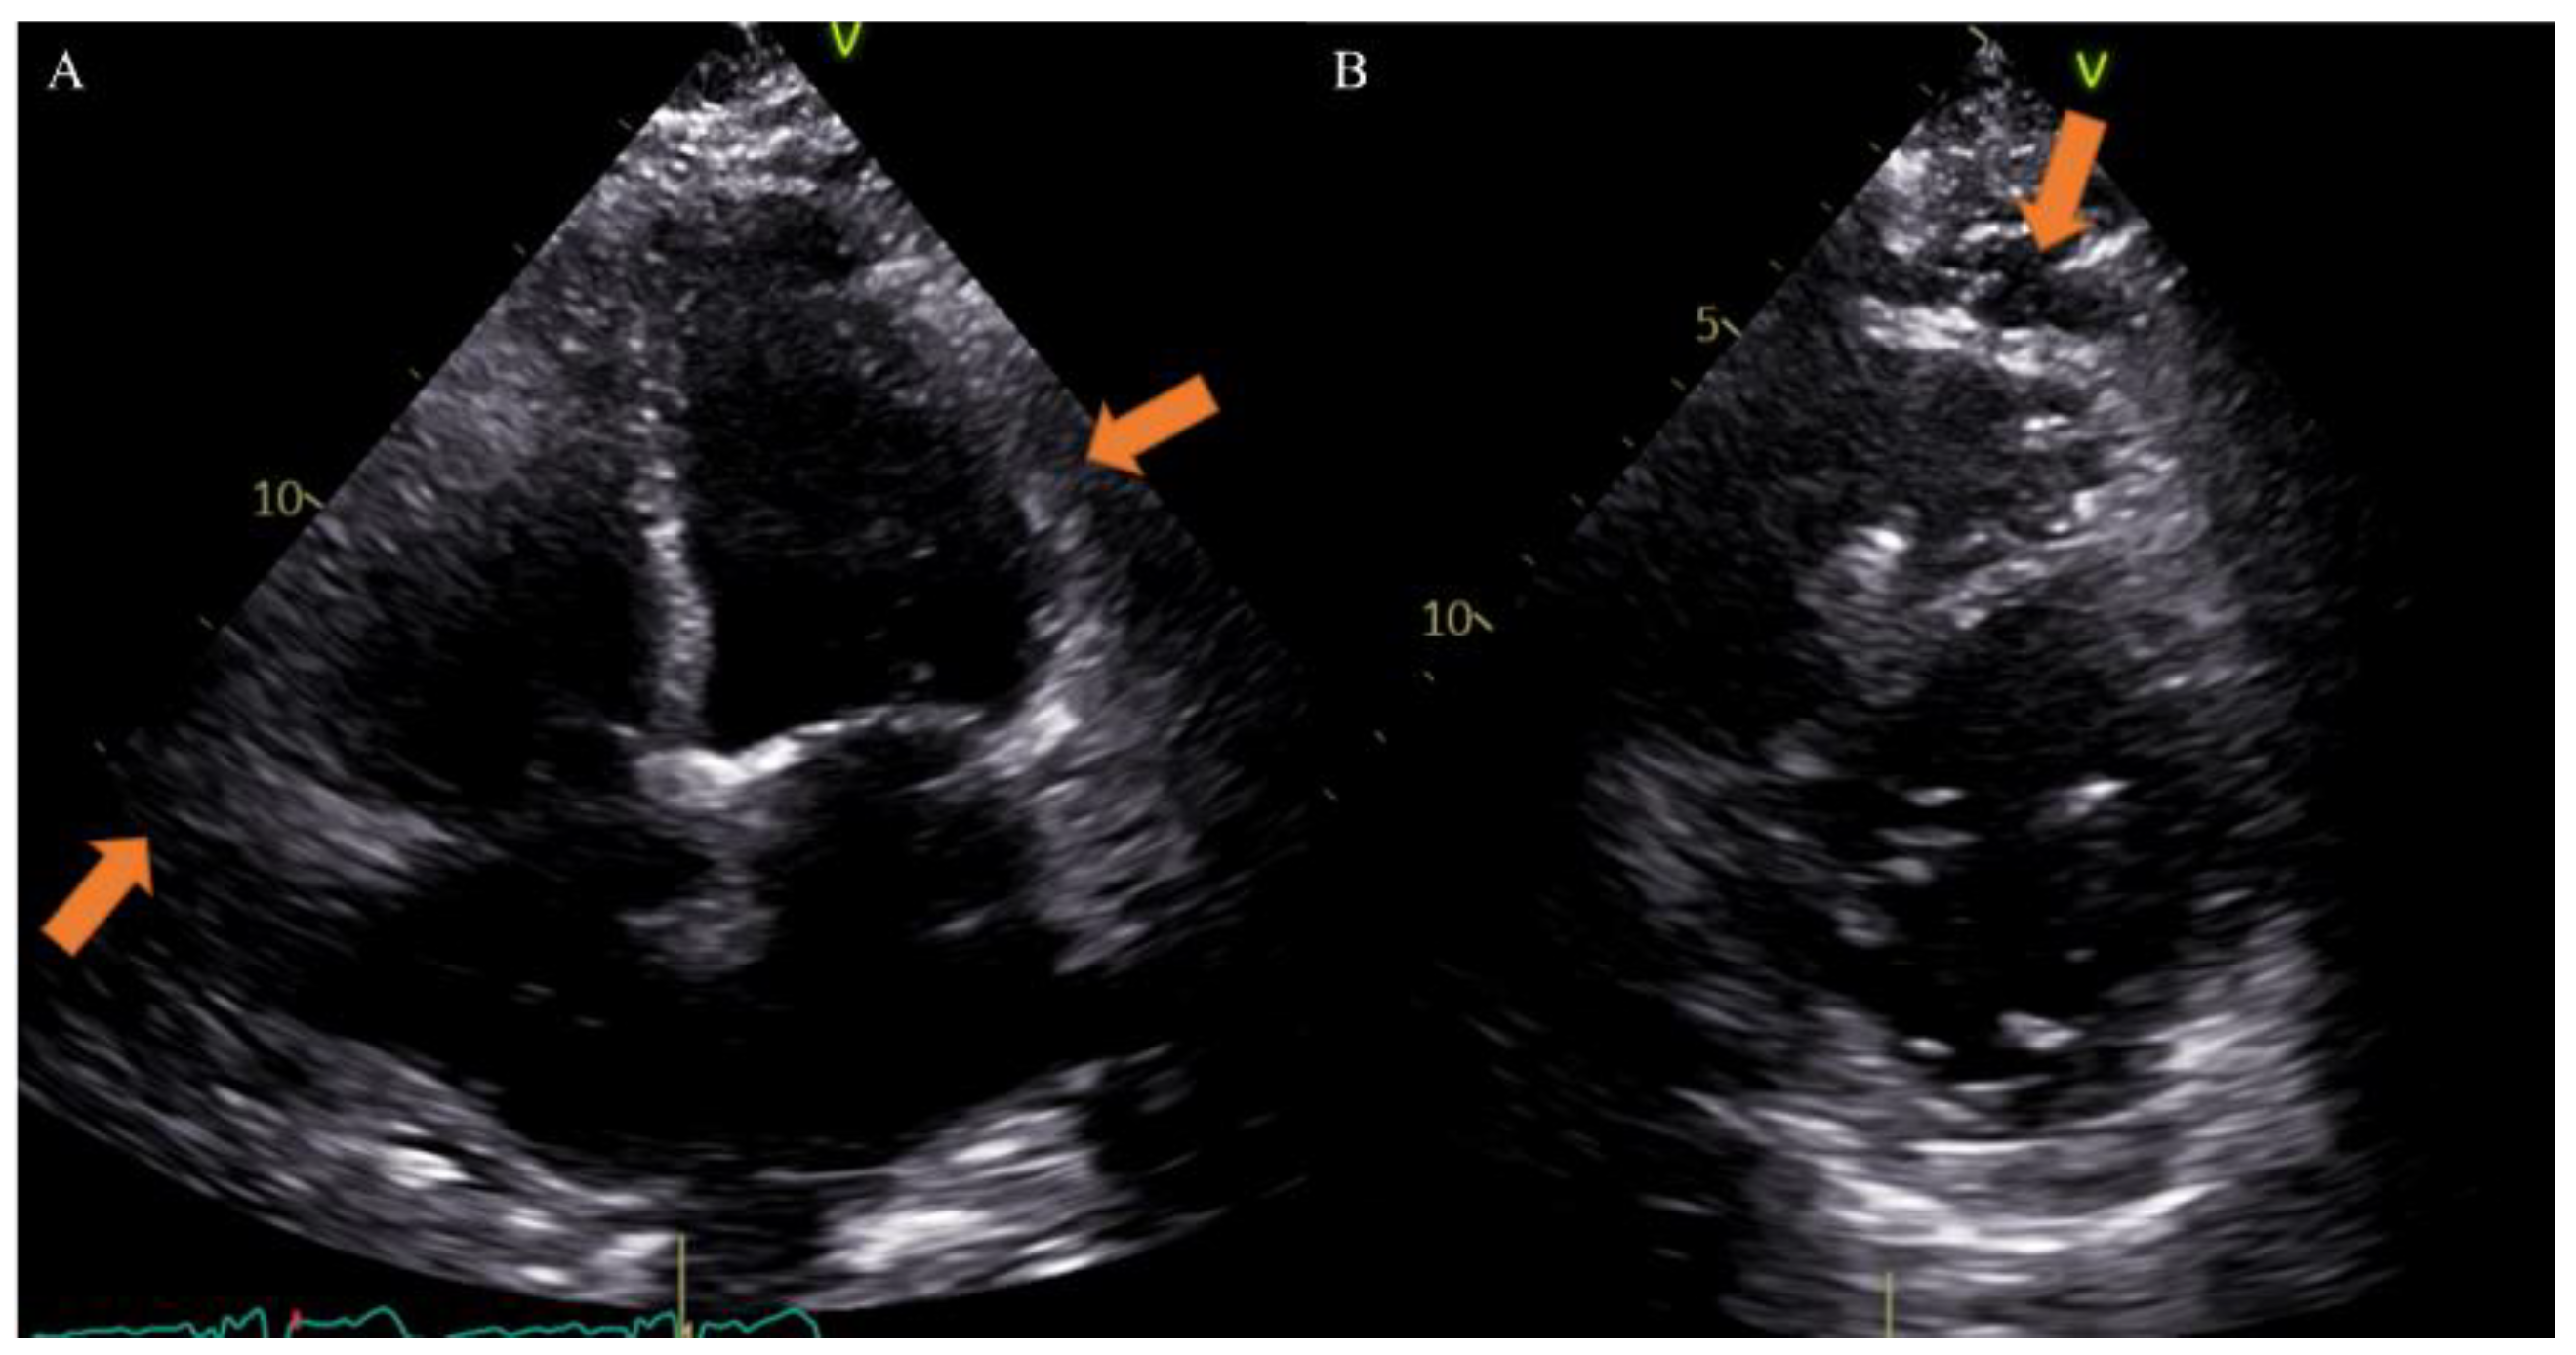

Different imaging techniques can study EAT and include echocardiography, cardiac magnetic resonance (CMR) and computed tomography (CT). Echocardiography is very useful to provide maximum thickness and provides a simple and easily accessible tool for EAT measurement, although it may not reflect the absolute amount of epicardial fat and gives less accurate results due to uneven distribution of epicardial fat and poor acoustic window [33]. Previous studies, however, have reported that echocardiographic measurement closely correlates with the total volume of EAT on other radiologic modalities and considering the great diffusion of this method in clinical practice, it could be very simple to obtain data on EAT [34] (Figure 2).

Figure 2.

Case of a 65-year-old male patient underwent to echocardiography showing epicardial fat tissue on four chambers ((A), arrow) and short axis ((B), arrow) views. From Giuseppe Muscogiuri’s private archive of unpublished cardiac imaging.

EAT is identified as the echo-free space between the outer wall of the myocardium and the visceral layer of the pericardium. According to the method first described and validated by Iacobellis et al., EAT thickness was generally measured perpendicularly on the free wall of the right ventricle at the end systole in 2–3 cardiac cycles. Maximum EAT thickness was measured at the point on the free wall of the right ventricle along the midline of the ultrasound beam, perpendicular to the aortic annulus [35]. Thickness varies among patients and usually ranges from 1 mm to 23 mm, but no definitive cut-off value has been identified [27]. For example, one study found a cut-off of 5.8 mm for predicting high-risk coronary plaques [36], while another reported that values of 9.5 mm in men and 7.5 mm in women could be considered thresholds to predict the metabolic syndrome [37]. On the other hand, CT and CMR can give also three-dimensional estimates of the overall EAT volume. In particular, the first shows higher spatial resolution and reproducibility but is limited by radiation exposure and long segmentation times, and the second is radiation-free but limited by lower spatial resolution and reproducibility, higher cost, and difficulties for obese patients [33,38]. However, thanks to different post-processing steps and without specific acquisitions, CT scans allow the calculation of EAT density, using Hounsfield Units (HU), both globally or on the perivascular coronary fat alone [26]. Moreover, the application of coronary CT angiography (CCTA) is rapidly increasing, following the ESC guidelines on the management of patients with suspicious coronary artery disease [39]. The availment of CCTA can provide data regarding coronary stenosis, plaque and characterization of EAT [5,40,41] (Figure 3).